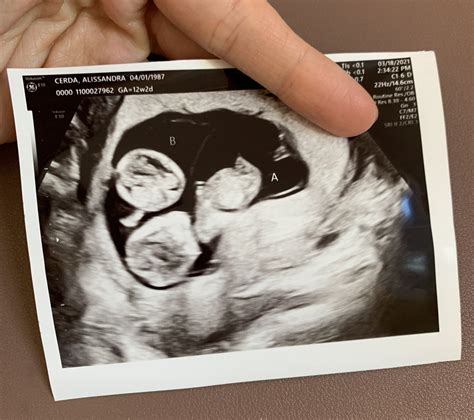

• Visualization of the Fetus: The sonographer will capture images of the fetus, including the head, abdomen, and limbs. These images help to assess the overall development and growth of the baby.

• Heartbeat Detection: One of the most exciting moments is hearing the baby's heartbeat. This is a reassuring sign that the fetus is developing normally.

• 12 weeks 2 days ultrasound